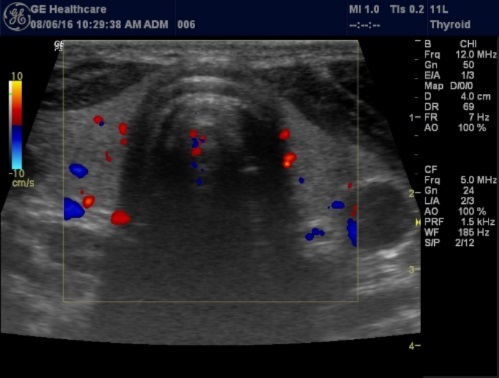

The superficial location of the thyroid gland renders it ideal for ultrasound examination 8. High resolution grey scale images can easily be obtained using high frequency transducer. In the transverse view, normal thyroid gland has the butter fly appearance, with left and right lobes connected with a narrow isthmus, Figure 1A. Both lobes can be imaged separately in the longitudinal plan, Figure 1B

Figure 1A.Normal thyroid gland transverse view

Histologically, if the excised gland has volume <500 mm3 it is said to be hyperplastic and if the volume is more than 500 mm3 it is nodular hyperplasia in 80% of cases26. In secondary HPT, the increase in the volume of parathyroid glands is associated with increase in vascularity, as evident in Color Doppler imaging 27.